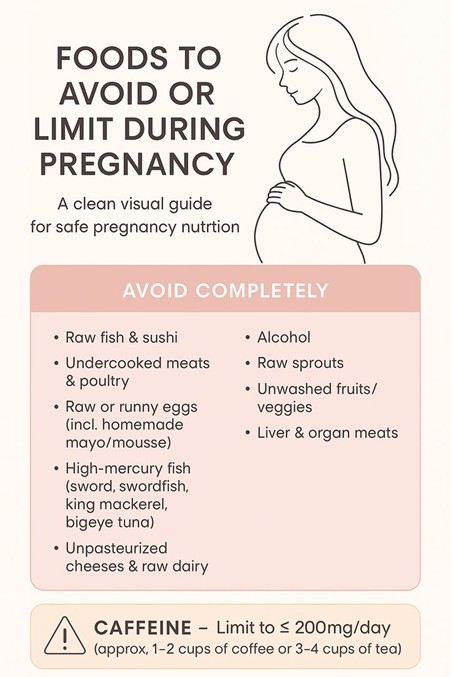

Choosing the Right Calcium Supplement

When selecting a calcium tablet during pregnancy, keep these points in mind:

- Check the composition: Calcium with vitamin D improves absorption

- Stick to trusted brands: Quality and testing matter

- Right dosage: Enough to meet daily needs, not exceed them

- Always consult your doctor, especially if you have medical conditions

How to Take Calcium Tablets Correctly

- Take 1–2 tablets daily, preferably after meals

- If taking more than 500 mg/day, split the dose (morning & evening)

- Keep a 2–3 hour gap from iron supplements

- Drink plenty of water

- Continue eating calcium-rich foods alongside

Are Calcium Tablets Safe?

Yes—when taken as prescribed.

Some women may experience mild constipation or bloating, which usually improves with water and fibre intake. Overuse, however, can cause issues like kidney stones or reduced absorption of other minerals.

If you have kidney problems, thyroid issues, or other medical conditions, speak to your doctor before starting supplements.

Consistency—not excess—is the key.